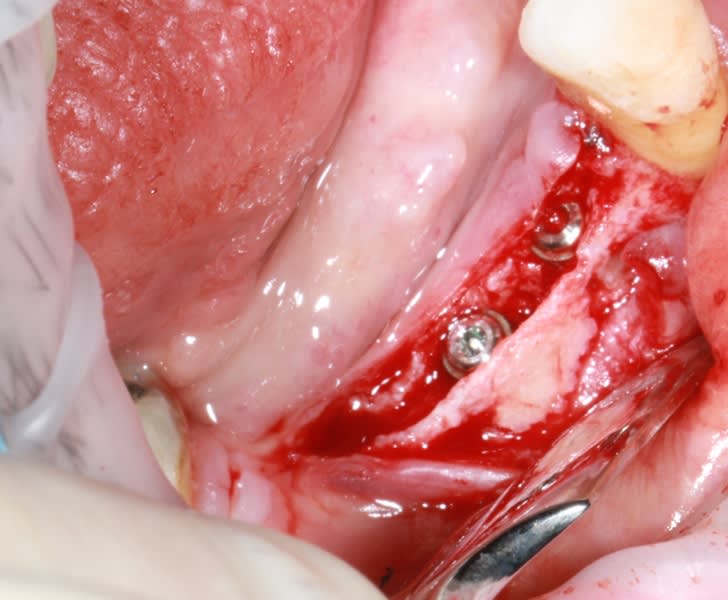

il y a eu un comblement fait il y a plus d'une dizaine d'année suite à la perte de la 21...

d'après ce que la patiente a dans son dossier médical, il semblerait que çà soit du RTR...

en tout cas 10 ans plus tard...il y a eu comme une "suspension temporelle", rien n'est intégré, çà n'est qu'un magma infâme....

donc, on nettoie (merci les fraises de dégranulation diam de chez dentogem...super efficaces), on pose l'implant et on fait une ROG avec des produits que je connais bien et qui marchent: Kasios TCP HP et membrane collagen AT

les clous sont aussi ceux de chez dentogem